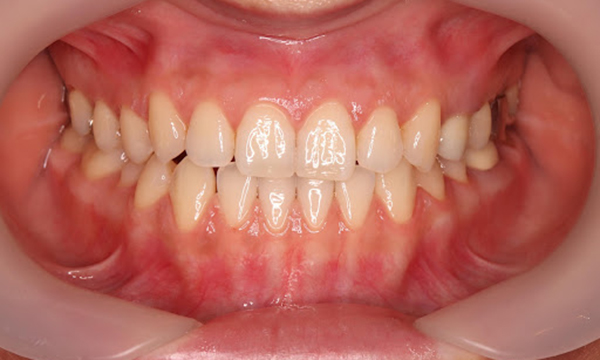

症例3

来院2回目、TBI後

症例

SRP後

初診時、TBI前

基本情報

年齢・性別 27歳・男性

主訴 主訴:左右下の歯ぐきに違和感がある

治療部位:全顎

治療内容 1.歯周基本検査、レントゲン撮影、口腔内写真、歯磨き指導、歯石除去、着色除去

2.SRP(スケーリングルートプレーニング)、再評価

その他

3.親知らずの抜歯

4.カリエス処置:右上1.2.3左上1.2.3右下6左下7CR(レジン充填)、右下7セラミックIn

5.定期検診

治療期間 6ヶ月

治療費 ※歯周基本治療の費用:PMTC以外保険診療3割負担

合計:19,680円

1.初診検査(歯周ポケット検査.レントゲン撮影):3,010円

2.歯磨き指導、歯面の歯石除去:1,410円

3.PMTC(自由診療):5,500円

4.SRP(歯周ポケット内の歯石除去)×4回:約2,000円/回

5.再評価:1,760円

(2023年12月現在)

リスク・副作用 ・最初は歯磨きをすると歯ぐきから出血するが毎日ホームケアを続けることで出血が徐々になくなる

・歯ぐきが腫れている状態が改善されると歯ぐきが引き締まり退縮するため、歯ぐきが下がったように感じることがある

・歯ぐきが引き締まると歯間が開いたように感じることがある

・歯ぐきが引き締まると知覚過敏の症状がでる可能性がある

・一度歯石を除去しても毎日のホームケアを怠ると再度歯石がつく

・治療後も再発を防ぐために定期的なメインテナンスが必要である

治療方針 1.初診検査(レントゲン撮影、口腔内写真、歯周検査、歯磨き指導)

2.歯磨きチェック、歯石除去、PMTC

3.SRP

4.再評価

特記事項 ・歯科医院は今回初めて

・タバコは24歳まで3年ほど吸っていたが健康のためにやめた

・親知らずは右下以外抜歯

・歯ブラシはルシェロP20M、補助用具はフロスを処方

担当者所見 全体的に歯と歯ぐきの境目に歯垢(細菌の塊)が残り、日々のホームケアで落とし切れていなかったことと、歯科医院への定期検診の習慣がなかったことから、全顎的な歯肉炎になってしまったと考えられる。

歯周基本治療とホームケアで歯ぐきの腫れや歯周ポケット、出血率などかなり改善されたが、出血がまだ0%ではない為、引き続き歯ブラシの当て方をお伝えしつつ今後は定期検診で3ヶ月おきに再発しないよう一緒に管理していく。